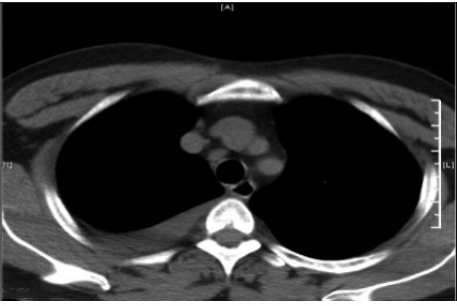

病史摘要:70 岁男性患者,因“反复肤黄尿黄 10 年余,咳嗽、胸闷 3 天”入院。既往有高血压、糖尿病史,2015 年服中成药后出现肤黄尿黄、肝功能异常,2024 年外院 MR 提示肝硬化,2025 年 4 月症状加重,多种指标异常,加用 UDCA 治疗;5 月我院诊断自身免疫性肝炎,予甲泼尼龙及吗替麦考酚酯治疗。此次入院前 3 天出现全身无力、头晕、咳嗽、胸闷。 诊疗过程:入院查体生命